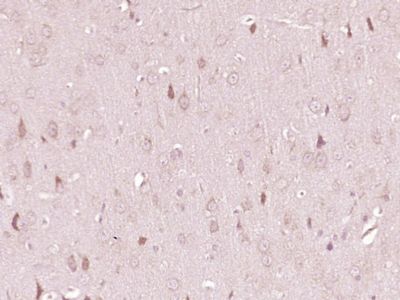

产品应用WB=1:500-2000 ELISA=1:500-1000 IHC-P=1:400-800 IHC-F=1:400-800 IF=1:100-500 (石蜡切片需做抗原修复)

色氨酸在脑中首先由色氨酸羟化酶(tryoptophan hydroxylase)催化生成5羟色氨酸(5hydroxytryptophan),再经脱羧酶作用生成5羟色胺,色氨酸羟化酶(TPH)是5-HT生物合成的限速酶,因此,色氨酸羟化酶的缺少可导致5-羟色胺的含量下降。色氨酸羟化酶主要在肝脏内代谢。

文献和实验,5-羟色胺能神经元的胞体在脑内的分布主要集中脑干的中缝核群,其末梢则广泛分布在脑和脊髓中。 (一)合成、贮存和释放 5-羟色胺的前体是色氨酸。色氨酸经两步酶促反应,即羟化和脱羧,生成5-羟色胺。此过程在某种程度上和儿茶酚胺的生成相似。 图14-9 5-HT的生成 色氨酸羟化酶象酪氨酸羟化酶一样,需要O2、Fe++以及辅酶四氢生物蝶呤。但脑内这种酶的含量较少,活性较低,所以它是5-HT生物合成的限速酶。此外,脑内5-HT的浓度影响色氨酸羟化